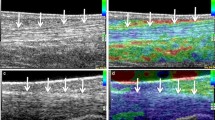

Physical examination and manual palpation are a part of clinical examination for assessing pathology with changes in tissue elasticity; EUS is a new development to demonstrate tissue stiffness under real-time conditions by measurement of tissue displacement. Ophir et al. first described the principle of strain imaging (“elastography”) in 1991 and in 1999, Pesavento et al. developed a fast cross-sectional technique, based on real-time elastographical imaging with clinical practicability [4–6]. The principle of EUS is as follows: tissue compression produces displacement within the tissue, which is less in harder tissue than in softer tissue. EUS is capable of visualizing different displacements by comparing an image pair before and after compression is applied on tissue [4–6]. Displacement is calculated in real-time by a modified US scanner in order that different grades of elasticity can be displayed over the conventional ultrasound image by using different colouring, e.g., yellow to red representing softer tissue in contrast to green and blue, which is found in harder tissue. New technical developments (e.g., for calculation of axial and lateral displacement of tissue structures under compression) allow for better spatial resolution, reduction of artefacts, and increased accuracy so that EUS can be usefully integrated in routine examinations [7].

Real-time sonoelastography was valuable in the detection of intratendinous and peritendinous alterations of lateral epicondylitis and facilitated differentiation between healthy and symptomatic extensor tendon [13]. Preliminary results revealed distinct softening of the symptomatic Achilles tendons when compared to healthy volunteers presenting with hard tendons structures [15] (Fig. 3a,b). However, this new technique has disadvantages and presents technical challenges. One major limitation is operator dependency because pressure is applied by using a free-hand technique, which might affect reproducibility. Moderating the pressure exerted with the ultrasound probe to avoid overly high and low pressures seems important. Near-proportional relationship between pressure exerted and tissue strain should be maintained; this can be monitored using the visual indicator scale on the machine, because when the pressure decreases or increases below a certain level, the pattern of the elasticity image starts to change drastically. Tissue shifting due to unilateral compression is another potential limitation, the use of a gel standoff pad can help to alleviate this problem.